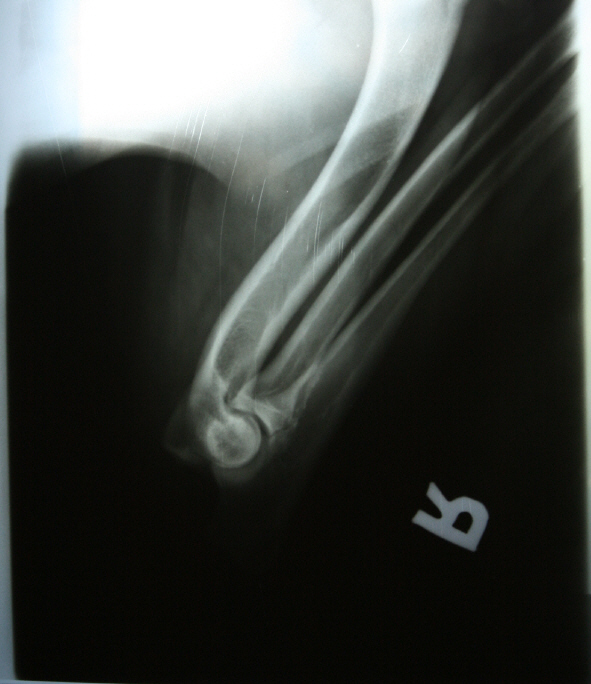

Allys Ellbogen gestreckt

ED: 0/0